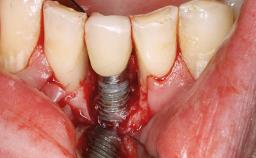

A 35-year old female patient was referred to the Department of Oral Surgery and Stomatology at the University of Bern, Switzerland, for examination of an implant site that had exhibited clinical signs of slightly delayed wound healing. In addition, the referring clinician found no evidence for a facial bone wall when she raised a flap to gain access to the implant for abutment connection. Four months earlier, she had inserted a bone-level implant in a single-tooth gap, where the lateral incisor had been extracted due to a chronic periapical lesion on the mesial aspect of the root. Implant placement was combined with simultaneous bone augmentation using deproteinized bovine bone mineral (DBBM, Bio-Oss®; Geistlich, Wolhusen, Switzerland) and a collagen membrane (Bio- Gide®; Geistlich), followed by primary wound closure. The patient also provided the postsurgical radiograph that displayed the implant with a 3.5-mm healing cap.